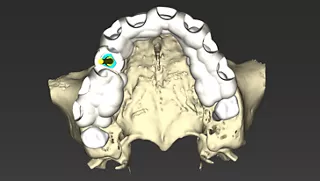

• Phase III: Digital implant planning using coDiagnostiX® for guided placement of an Axiom Bone Level implant with Healfit® SH healing abutment and simultaneous connective tissue grafting to enhance peri-implant stability (Fig 2 a&b, 3 a-c).

2a. 2b. Implant and Healfit® SH planning in coDiagnostiX®.

2a

2b

3a. 3b. 3c CAD design of the tooth-supported surgical guide in coDiagnostiX®. Superimposition of the guide on the 3D bone model for fit verification prior to fabrication.

3a

3b

3c

Phase III: Guide design (Fig 3a. 3b. 3c) for guided Implant Placement and Soft-Tissue Augmentation